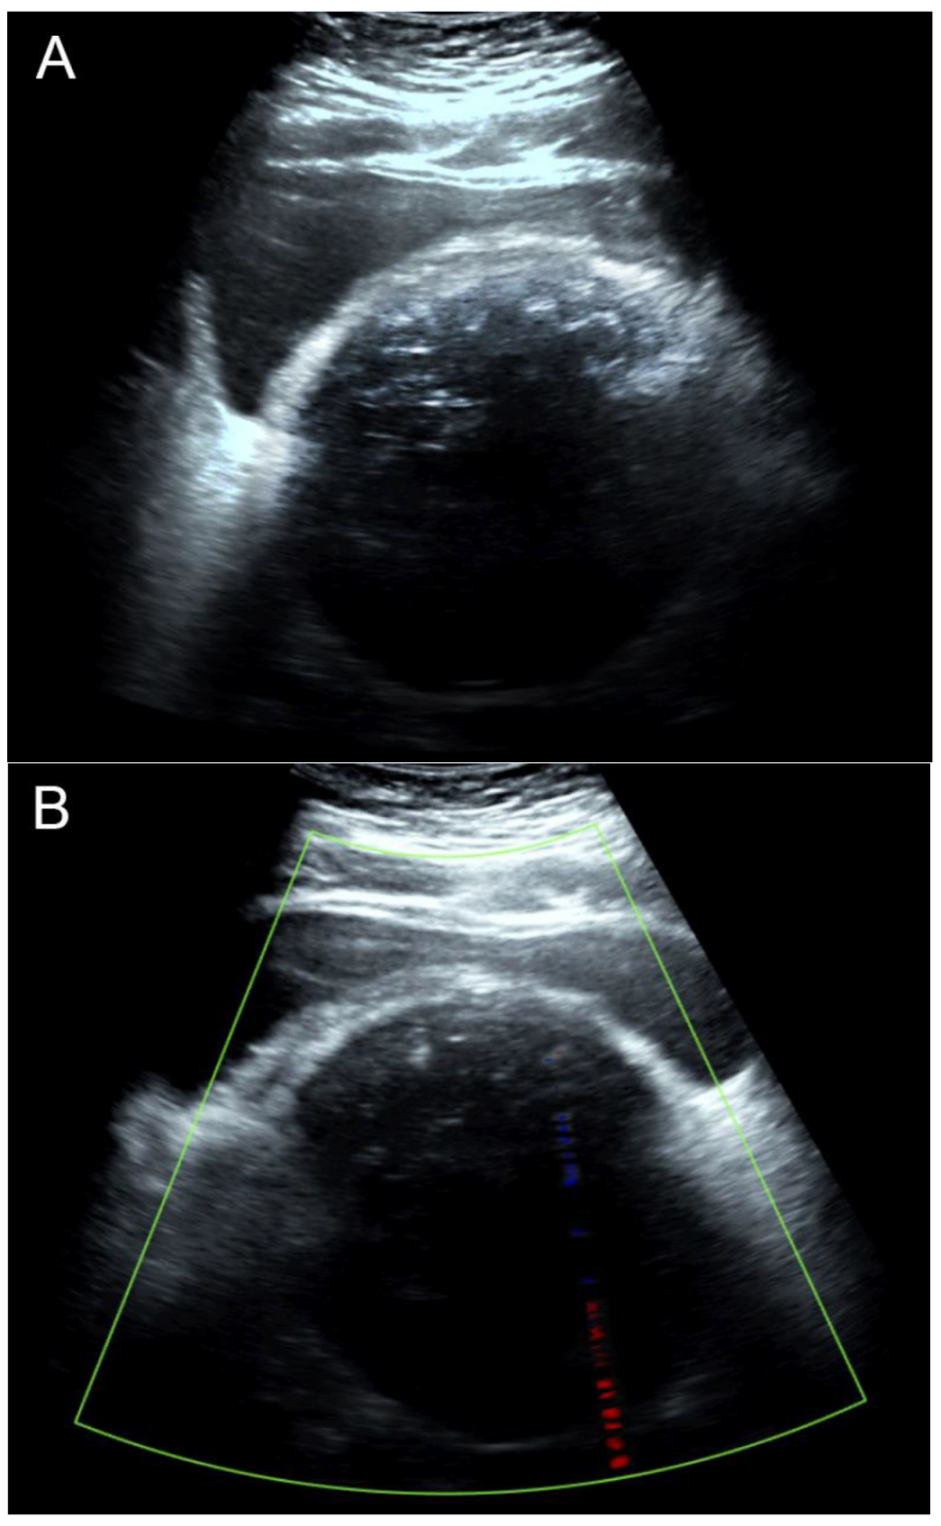

Figure 2. Transabdominal ultrasound images: (A) The 2D ultrasound showed a pelvic mass of uncertain anatomical origin, with severe acoustic shadow, obscuring all details behind the calcifications on the surface of the mass. (B) Color flow mapping showed no vascularization. Note that there were no multiple-edge shadows typical for uterine leiomyomas because multiple calcifications completely obscured all of the structures underneath the surface facing the ultrasound beam. The ultrasound beam cannot pass through several layers of calcific discrete pellets. Accordingly, the popcorn appearance cannot be produced by ultrasound, and the examination should be considered suboptimal and non-informative. Though uterine leiomyomas can sonographically be diagnosed with confidence in most cases, severely calcified leiomyomas can be a diagnostic challenge because of suboptimal and non-informative examinations.